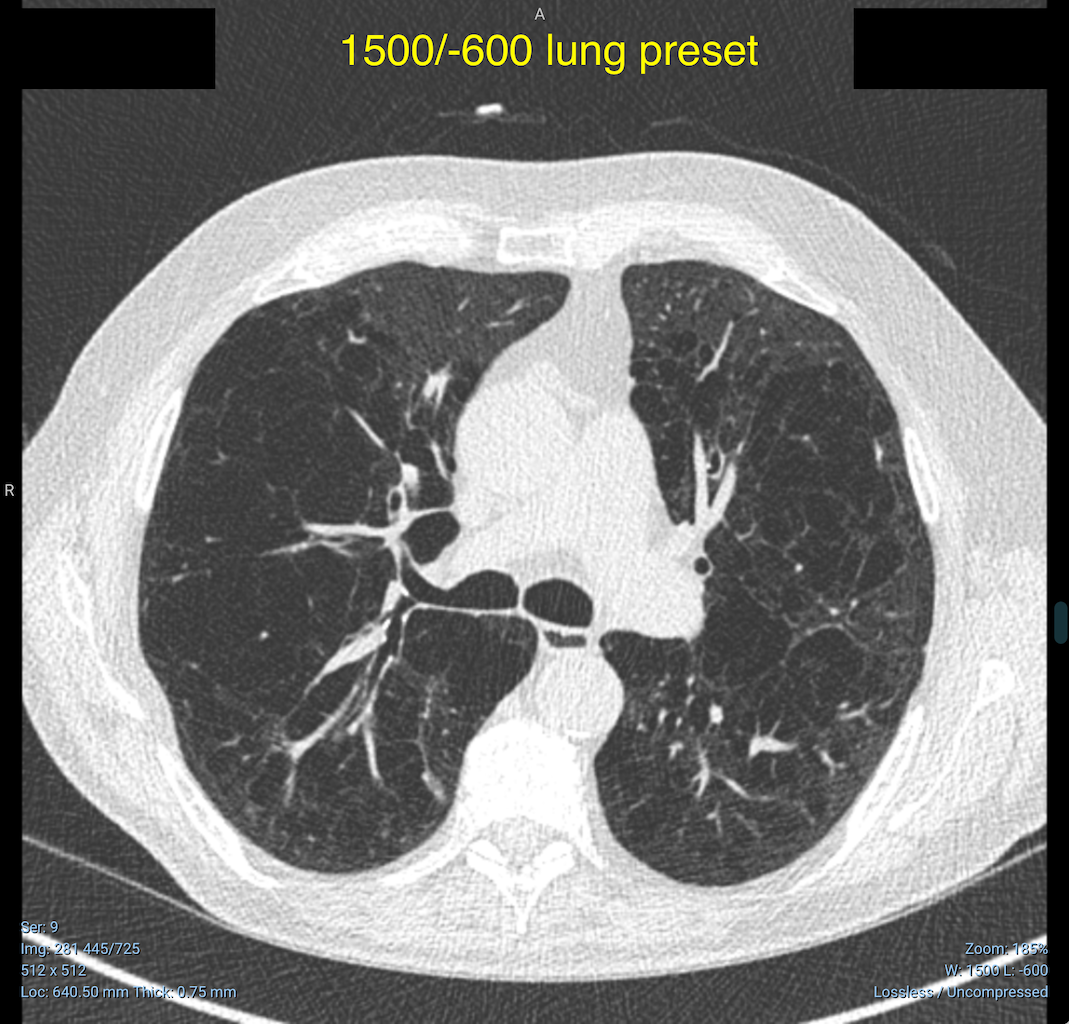

Incorrect Default Preset For Lung Window Level Issue 3177 OHIF